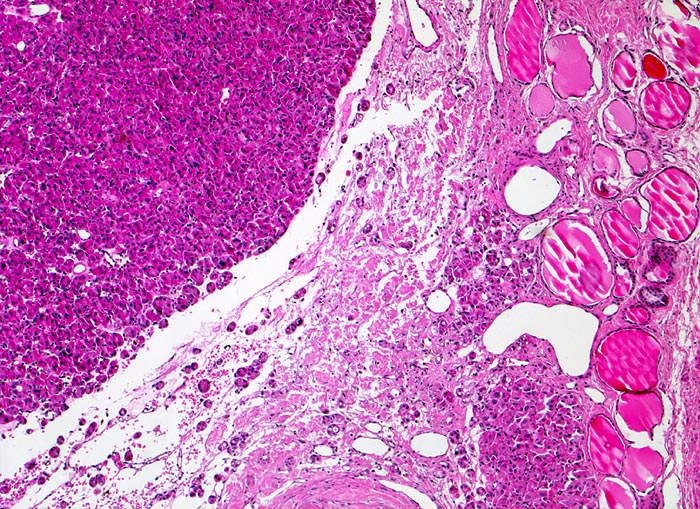

Das Karzinom erscheint als solide zellreiche Tumormasse und unterscheidet sich morphologisch deutlich vom angrenzenden makrofollikulären Parenchym. Die breite Tumorkapsel wird von malignen Follikeln durchsetzt. Jenseits der Kapsel ist Tumorgewebe erkennbar, das die Kapsel durchbrochen hat und unmittelbar an das normale Parenchym angrenzt.

Ein follikuläres Schilddrüsenkarzinom kann bewiesen werden, wenn entweder (1) die Kapsel des follikulär gebauten Knotens vom Tumor durchbrochen wird und das Karzinomgewebe das angrenzende Schilddrüsengewebe infiltriert oder (2) Tumoreinbrüche in Gefässe (meistens Kapselvenen) nachweisbar sind oder (3) der Tumor bereits makroskopisch klar invasiv wächst (grob invasives Karzinom)